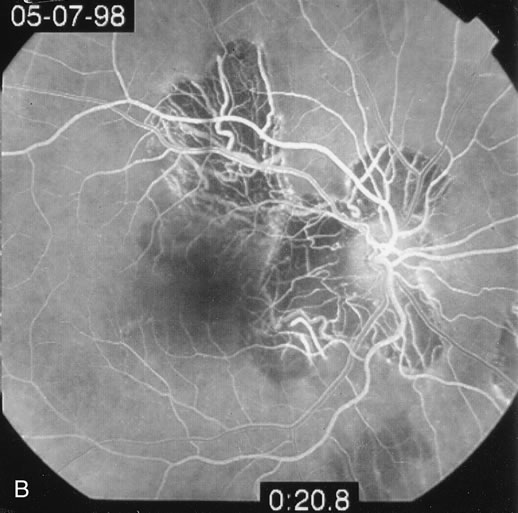

DIFFUSE SUBRETINAL FIBROSIS

Some patients present with subretinal bands that extend between chorioretinal scars. In addition there may be initial active yellow choroidal lesions that subsequently become atrophic. Vitreous cells are usually present although they may be few and difficult to detect. Visual acuity loss in these cases may be due to active choroidal neovascularization, subretinal bands under the fovea, or from cystoid macular edema. The vast majority of affected patients are women with a mean age of 27 years and both eyes are usually involved. The affected individuals tend to be myopic.49 The age range is from 6 years to 76 years and there is no racial predilection.40 Whether it is a separate disease or a more severe form of multifocal choroiditis is controversial (Figs. 10 and 11). Aggressive therapy is warranted because it has a poorer prognosis than most cases of multifocal choroiditis. This syndrome has been called either diffuse subretinal fibrosis or progressive subretinal fibrosis syndrome.

Fig. 11. A. Subretinal fibrosis in a case of multifocal choroiditis. B. Fellow eye showing classic coalescent hyperpigmented chorioretinal scars of multifocal choroiditis. These scars also can be seen in presumed histoplasmosis syndrome, but the subretinal fibrosis is extremely rare in presumed ocular histoplasmosis syndrome (POHS).